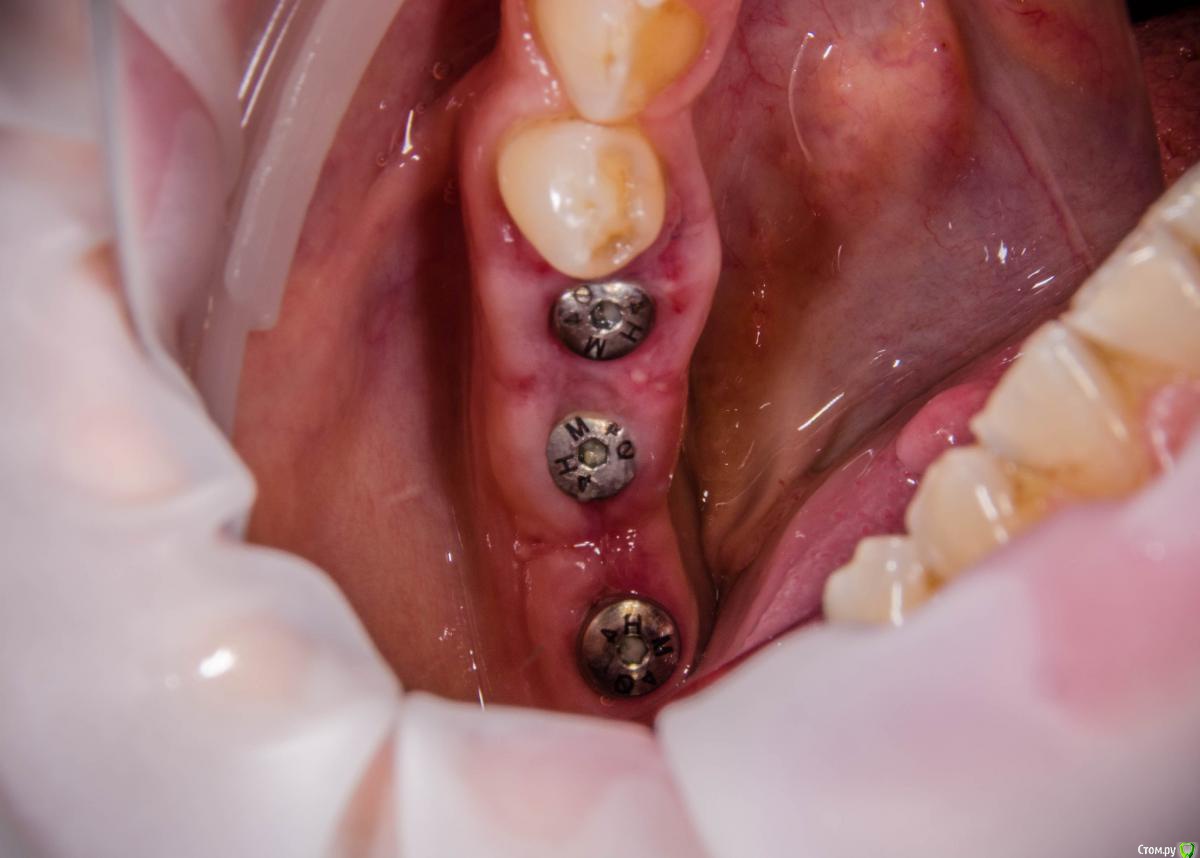

kamranchick Опубликовано 8 февраля, 2017 Автор Поделиться Опубликовано 8 февраля, 2017 А что и какой размер ставили?Послабляющий распил не делали?я тут не делал распилы, тут нет расщепления3,5-8,5 Ссылка на комментарий

kamranchick Опубликовано 8 февраля, 2017 Автор Поделиться Опубликовано 8 февраля, 2017 Спасибо за публикацию.Какова ширина гребня?5мм сверху в области кристального модуля имплантата дальше около 7мм) Ссылка на комментарий